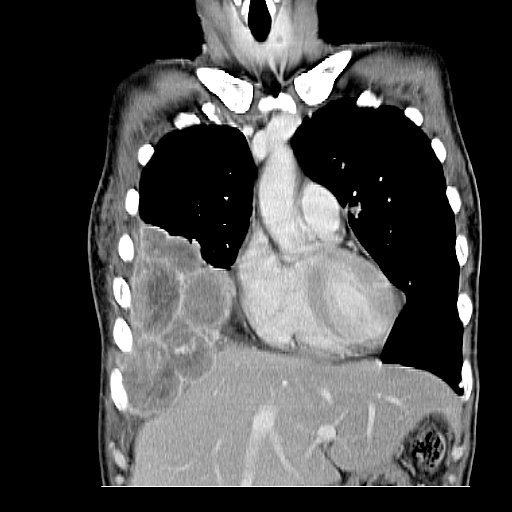

【110-2 醫學(五) 第73題】有關下圖的敘述,下列何者錯誤?

詳解

破題關鍵

這張圖是胸腹部的電腦斷層掃描冠狀切面,解題核心在於判斷圖中是否有明確呈現下行主動脈。仔細觀察可以發現,雖然有顯影劑,但這個切面主要顯示心臟和肝臟,下行主動脈並不明顯。

選項拆解